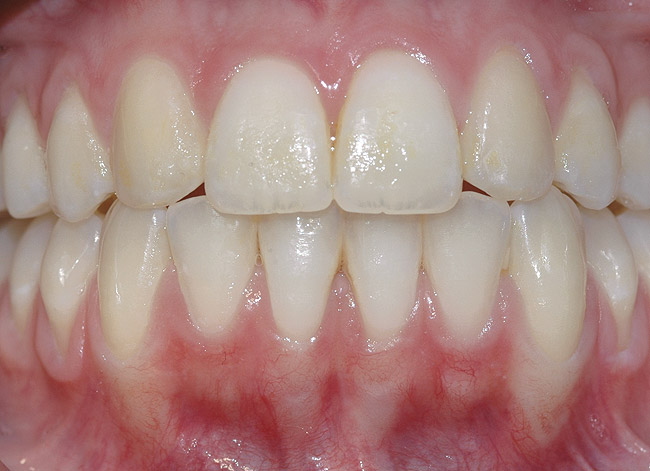

CASE 1 Fig 2. Pre-treatment clinical view of a 28-year-old patient with Miller Class I recession of the lower left central incisor treated with conservative SPT.

Figure 2

Fig 3. Two-year follow-up of same patient shows spontaneous root coverage.

Figure 3

When the tooth is properly aligned within the arch, treatment is managed with reference to Miller’s classification.7 Because most post-orthodontic GR cases are classified as Miller Class I and II defects, the authors focus on the management of these two classes only, and within the scope of this article, Miller Class III and IV defects are not addressed. Surgical root coverage of both Miller Class I and II defects is one treatment choice. However, in Miller Class I cases, a conservative approach can be considered, as well. Such an approach consists of supportive periodontal treatment (SPT)—professional periodic deposit removal every 2 to 3 months during a 1- to 2-year period. The authors’ clinical experience shows that spontaneous root coverage may occur following this conservative approach, particularly in young patients (Figure 2 and Figure 3). Similar results have been reported in a 3-year prospective study in which recession defects healed spontaneously following improvement in oral hygiene standards in children.30 In cases in which no root coverage is observed at the end of the follow-up period, surgical root coverage can be considered.